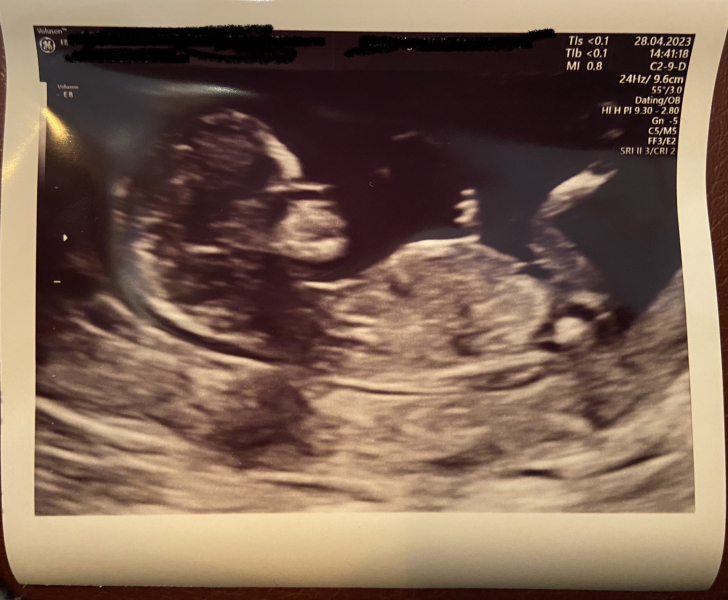

seven201 · 28/04/2023 15:22

Still no NIPT results but here's a scan photo. Very underwhelming scan after yesterday's one, just very quick and no explaining things. But no concerns raised.

@seven201 beautiful 💕

@seven201 Ahhh, lovely photo! 💗Thank you for sharing - it spurs me on a bit! Sorry you felt rushed and also that your NIPT results haven't come. Hopefully they come in soon. For now, I think a wee celebration of this milestone is in order! Especially after everything you've been through!